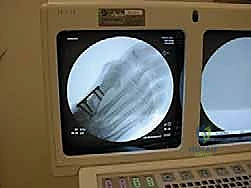

صورة توضيحية لـ عملية قطع عظم شيفرون الداني بالصفيحة المغلقة: حل جذري لإبهام القدم الأروح

![صورة توضح الصفيحة المغلقة في عملية شيفرون](/media/hutaif_opertive/hutaif-ch11-proximal-chevro-p

صورة طبية: عملية قطع عظم شيفرون الداني بالصفيحة المغلقة: حل جذري لإبهام القدم الأروح